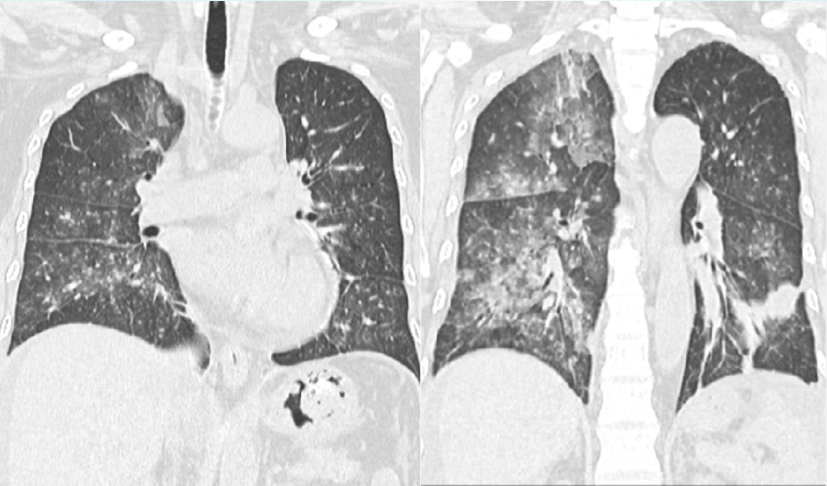

入院当天送KL-6快速进行性升高(图4)患者肺部后续出现机化和纤维化(图5)尽管整个治疗过程非常艰辛但最终预后比较满意。随访胸部CT可见病变吸收良好。

图片

5  患者住院期间胸部CT变化情况